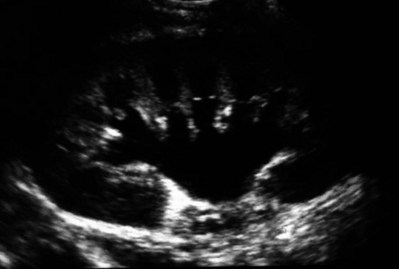

CT scan is frequently obtained for any patient presenting with acute flank pain (Fielding et al, 1997; Dalrymple et al, 1998; Vieweg et al, 1998) (Fig. 41–3). Moreover, CT scans provide detailed anatomic and functional information to aid in diagnosis of UPJ obstruction (Fig. 41–4A-C). Both ultrasonography and CT scanning also have a role in differentiating acquired causes of obstruction such as radiolucent calculi or urothelial tumors. In neonates and infants, the diagnosis of UPJ obstruction has generally been suggested either by routine performance of maternal ultrasonography or by the finding of a flank mass. In either setting, renal ultrasonography is usually the first radiographic study performed. Ideally, ultrasonography should be able to visualize dilatation of the collecting system to help differentiate UPJ obstruction from multicystic kidney and determine the level of obstruction. UPJ obstruction and multicystic kidneys are distinguishable in the majority of cases by ultrasound alone. With UPJ obstruction, the pelvis is visualized as a large, medial sonolucent area surrounded by smaller, rounded sonolucent structures representing dilated calyces. At times, dilated calyces will be seen connecting to the pelvis via dilated infundibula (Fig. 41–5).

Figure 41–5 Classic ultrasound image of ureteropelvic junction obstruction, with dilated renal pelvis and infundibula and calyces. Note the ureter is not visualized in this image.